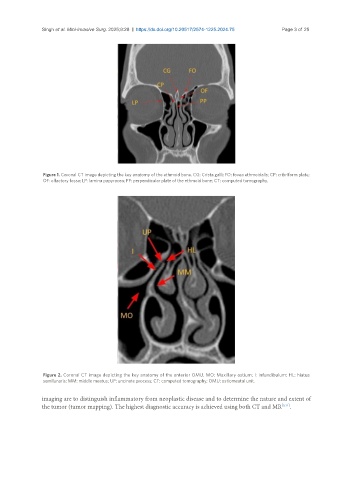

Figure 1. Coronal CT image depicting the key anatomy of the ethmoid bone. CG: Crista galli; FO: fovea ethmoidalis; CP: cribriform plate;

OF: olfactory fossa; LP: lamina papyracea; PP: perpendicular plate of the ethmoid bone; CT: computed tomography.

Figure 2. Coronal CT image depicting the key anatomy of the anterior OMU. MO: Maxillary ostium; I: infundibulum; HL: hiatus

semilunaris; MM: middle meatus; UP: uncinate process; CT: computed tomography; OMU: ostiomeatal unit.